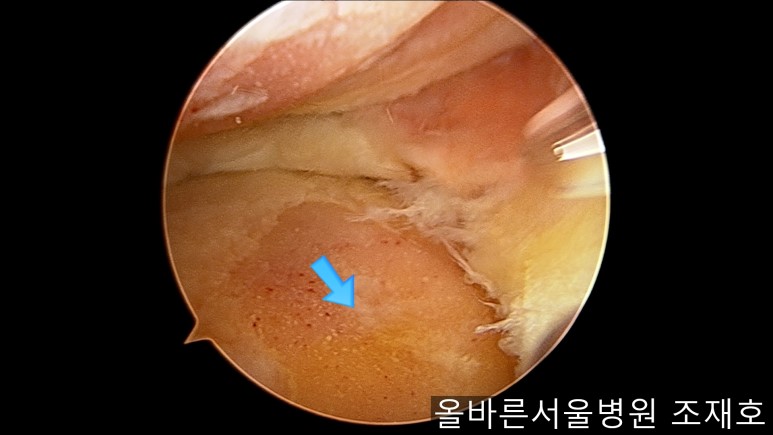

通过关节镜图像可看到:由于内侧股骨髁软骨损伤骨头已经显露出来。

image_9824311181519375935940.jpg

胫骨上端的软骨损伤严重,也露出了骨头。

image_9926851221519375935929.jpg

正是缺失软骨的部位碰到一起,引发剧烈疼痛,腿部逐渐变形。